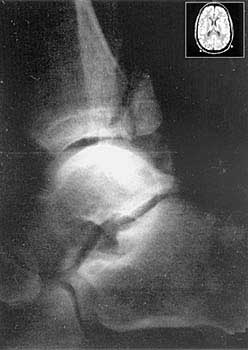

В 1972 г. Лаутербур получил первое в мире двухмерное ЯМР-изображение двух стеклянных капилляров, заполненных жидкостью (правда, на это ушло более 4 часов). Через год он опубликовал в журнале “Nature” статью, в которой были представлены трехмерные изображения объектов, полученные по спектрам протонного магнитного резонанса (ПМР) воды из этих объектов. Эта работа и легла в основу метода магнитной резонансной томографии (МРТ). Первые томографы для исследования тела человека появились в клиниках в 1980-1981 гг., а сегодня томография стала целой областью медицинской диагностики (рис.1).

Рис.1. Томограммы среза мозга человека (на врезке)

и голеностопного сустава с переломом.